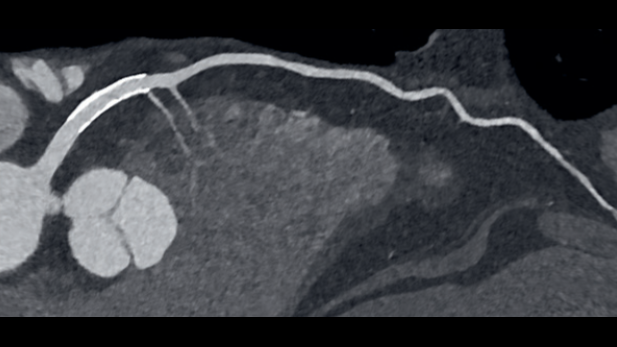

Innovating personalized care along the patient journeyCardiovascular diseases remain the leading cause of death worldwide and continue to contribute to increasing costs in healthcare systems.1 To improve your personalized cardiovascular care delivery, make precise risk assessments, enhance diagnostic confidence, and make well-informed therapy decisions we are committed to partnering with you and providing holistic state-of-the-art solutions.

Our connected cardiovascular care solutions portfolio empowers you to focus on each individual patient and deliver the precise care they need along the entire patient journey.